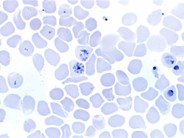

A 61-year-old female patient with an uneventful medical history was admitted to the emergency department because of icterus and abdominal discomfort. Upon arrival, she was hemodynamically stable. No laboratory tests could be performed because of a massive hemolysis (panel A), so the decision was made to perform a direct blood smear, which showed 2 species of bacteria and erythrophagocytosis (panels B and C). The patient deteriorated acutely and was admitted to the intensive care unit, where she was intubated and started on massive inotropes and broad-spectrum antibiotics, under the hypothesis that she was in septic shock. Repeated blood samples showed severe hemolysis with no possibility of chemical or hematologic testing. The patient died within 1 hour as a result of overwhelming sepsis. Postmortem blood cultures showed Clostridium perfringens and Escherichia coli bacteremia. The autopsy revealed an infected hematoma in the liver hilum as the source of the sepsis. Clostridium septicemia is known for its massive hemolysis and poor prognosis. This case shows that a direct blood smear can be a fast and relevant test to diagnose severely ill patients.